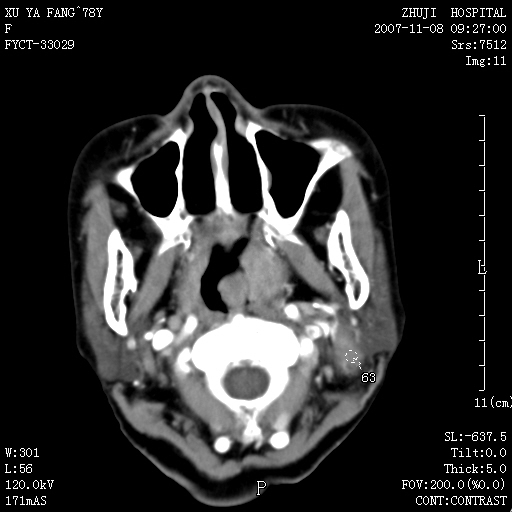

女性,78y,发现左侧扁桃体区肿大,表面糜烂.及颈部肿块一周.

左侧扁桃体恶性肿瘤伴淋巴结的转移;考虑为扁桃体癌可能。此部位的恶性肿瘤以扁桃体癌和淋巴瘤多见,相对来说淋巴瘤范围较广泛些。有时两者区别较难,需要活检。

左侧扁桃体区软组织占位,强化后边界清晰,密度均匀,周围脂肪间隙清晰。周围淋巴结肿大。首先考虑扁桃体炎性增生,不排除扁桃体区的恶性肿瘤!!不知临床上有无发烧??/wbc是否增高??

左侧口咽侧壁巨大软组织肿块突入口腔,增强密度均匀,中度增强,左颈部多发肿大淋巴结,考虑左侧扁桃体恶性肿瘤(淋巴瘤还是癌不好鉴别)并淋巴结转移。 期待病理!

结果淋巴瘤-----学习了